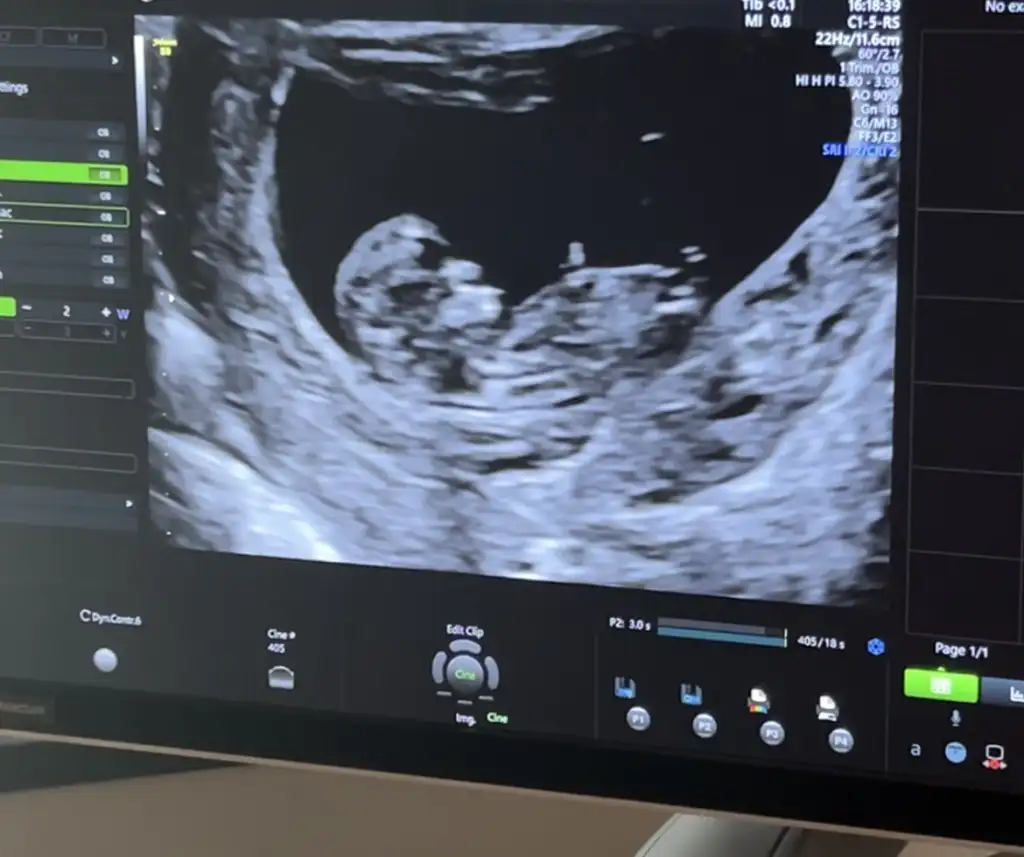

Ay rica etsem banada bakar mısınız 12+1 ultrason resmi vermedi doktor videodan ekran görüntüsü aldım

Eklentiler

• 1C137FD4-59C1-4330-B9C9-70DA2F47F751.webp

16,1 KB · Görüntüleme: 275

• 0ABF3CE7-3E16-417C-9809-E34E028AE0F8.webp

14,4 KB · Görüntüleme: 238

• 4A46BE13-077D-4603-83C2-E3A431874A5B.webp

13,9 KB · Görüntüleme: 236